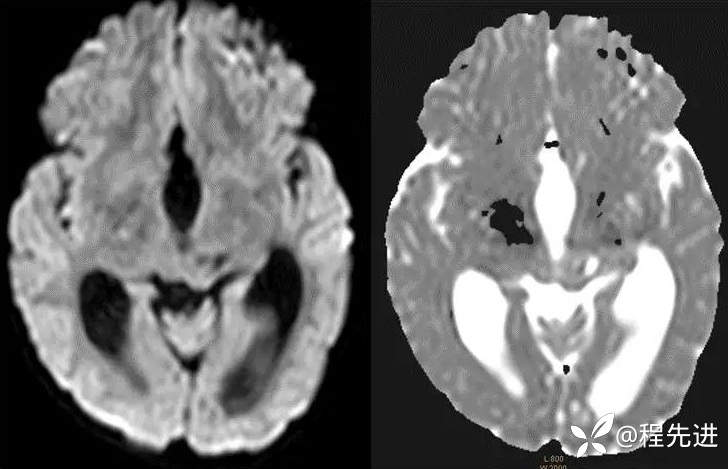

CT